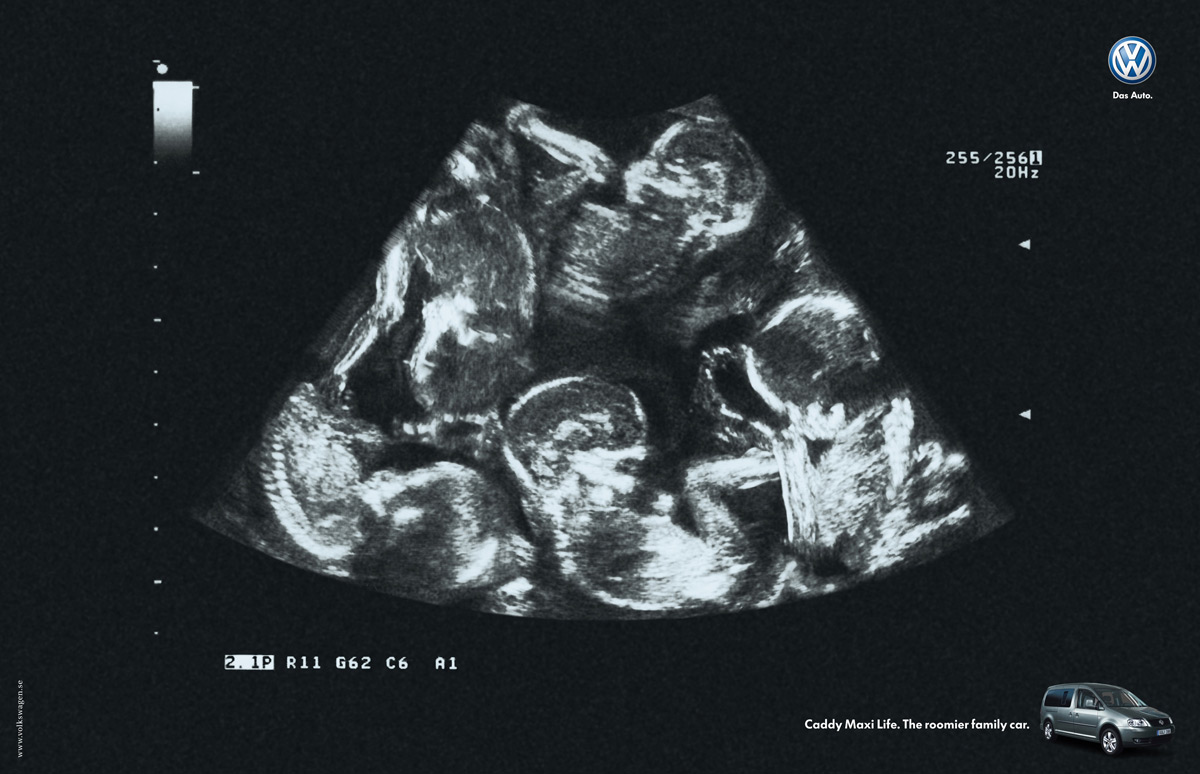

Sextuplets Ultrasound 30 Weeks Vaginal ultrasound: twin pregnancy 8